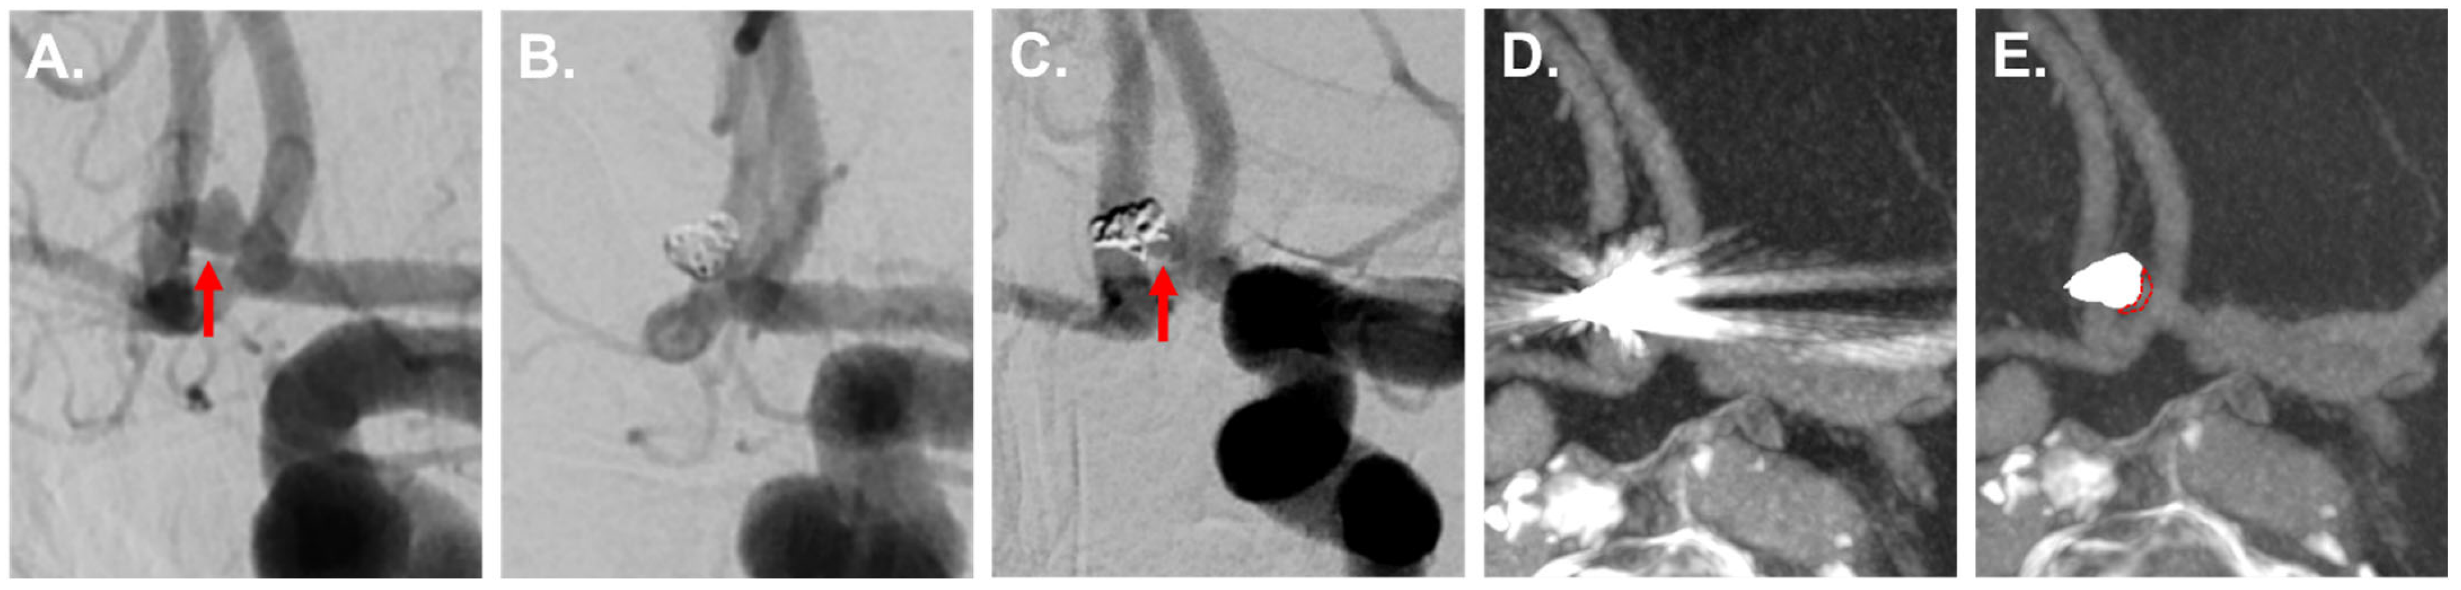

3.3.2. IAs Treated via Clipping